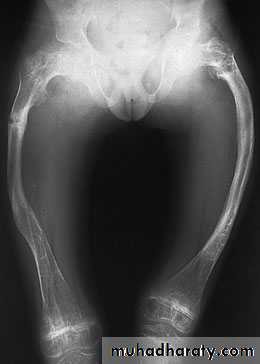

Long-bone deformities are common, these may require operative correction, usually by 4 or 5 years of age. osteotomies are performed and the bone fragments are then realigned on a straight intra medullary

rod; the same effect can be achieved by closed osteoclasis.

The problem of the bone outgrowing the rod has

been addressed by using telescoping nails; however,

these carry a fairly high complication rate.